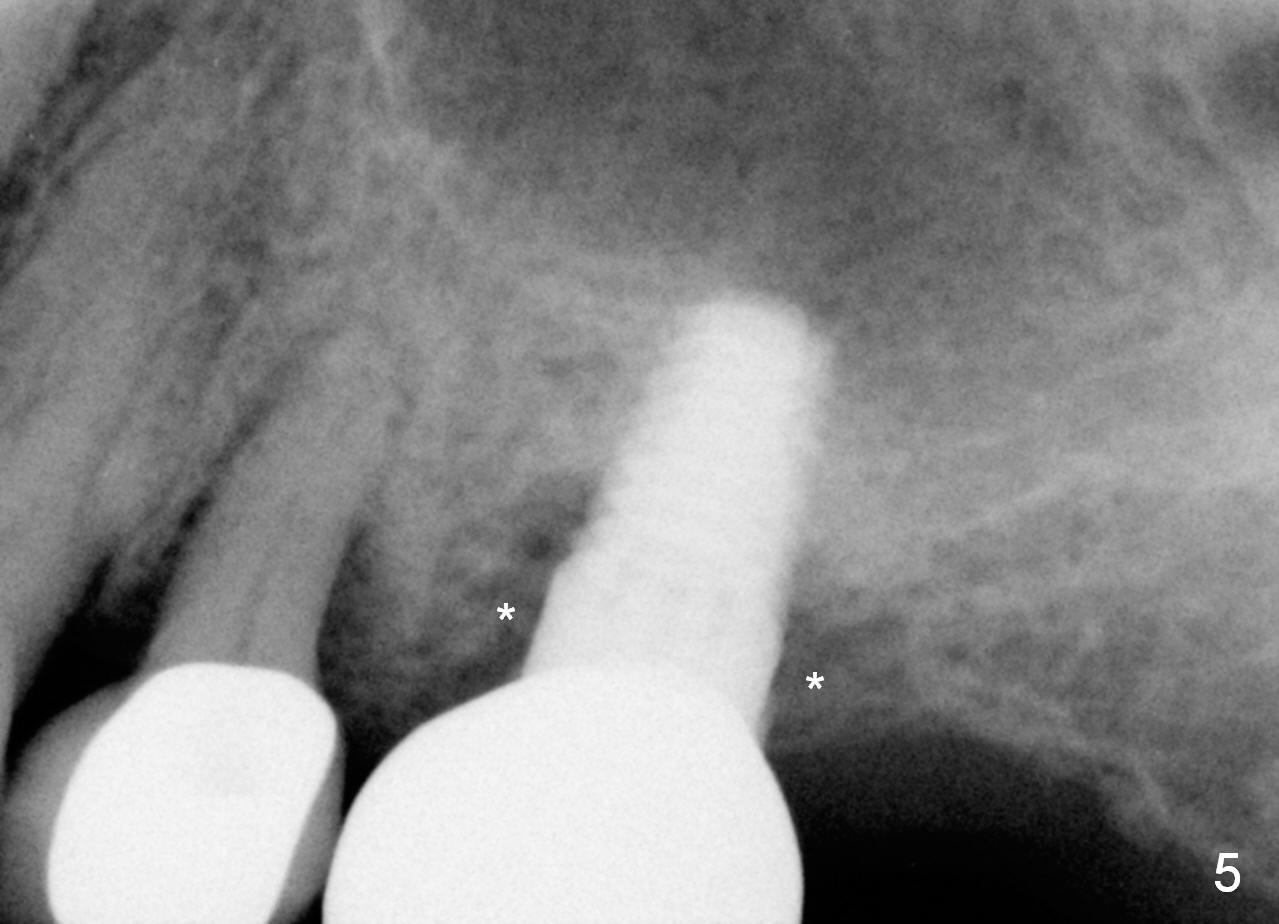

Mrs. Goh (71 years old) has lost 4 upper molars (Fig.1,6). The 1st sign of overload is increased periodontal space around the tooth #13 (Fig.1 *). The best way to tackle the overload is to place 4 implants. The 1st step is for the site of #14 (Fig.2: design; Fig.3: 4.5x11 mm tap; Fig.4: 5x11 mm implant). The 2nd sign of overload is repeated dislodgement of the implant supported crown. The 3rd sign of overload is bone loss around the implant 6 months post cementation (Fig.5 *). The 4th sign of overload is subgingival crown fracture of the tooth #5 (Fig.6).